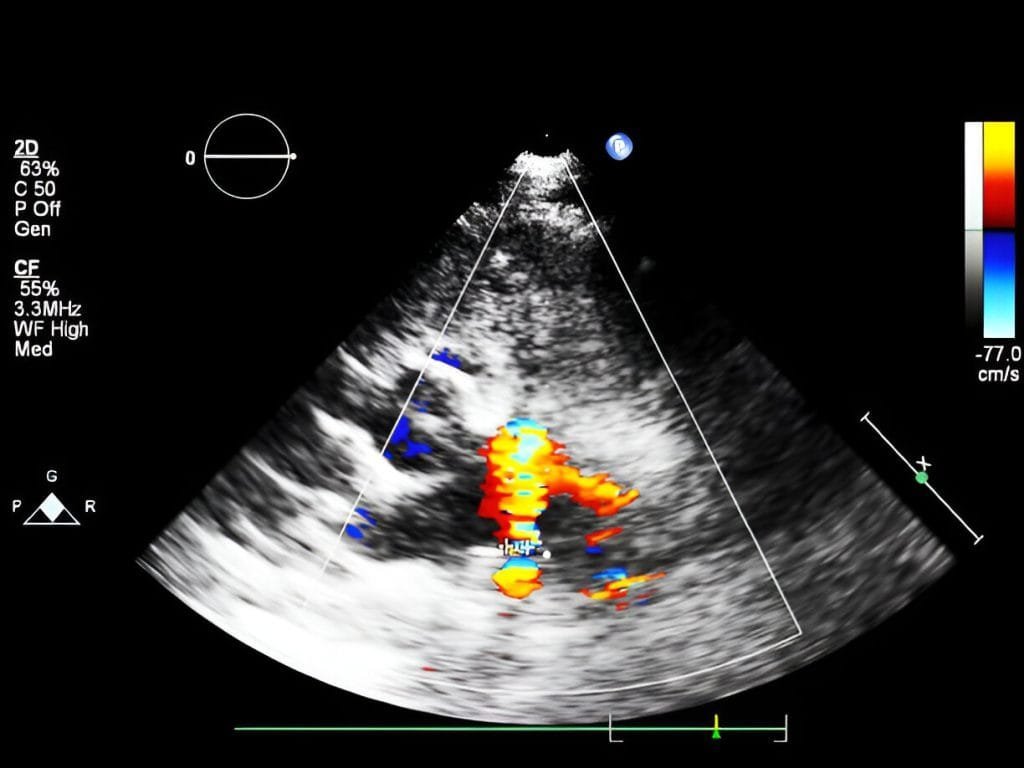

This imaging procedure helps doctors detect abnormalities and monitor heart conditions. The test used high-frequency sound waves to generate real-time, moving images of the heart.

• Evaluates blood flow patterns: The test detects abnormal blood flow, blood clots, or shunts (abnormal passages between chambers).

A technician performs the 2D echo test. During the test, a get is applied to the chest, after which a transducer (a handheld device) is placed. This device sends ultrasound waves that bounce off the heart, which are then converted into images on a monitor and can now be assessed.

These are real-time images that provide information about the size and shape of the heart, its pumping strength, valve health and the overall functioning of the heart. From these images, doctors can identify associated abnormalities.